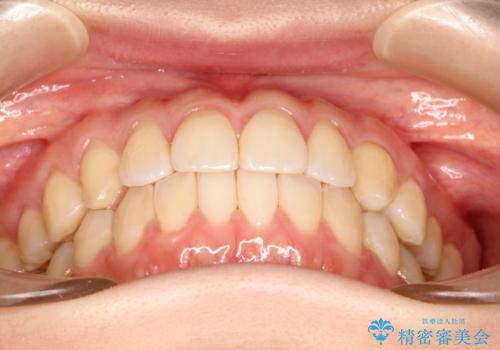

主に歯列弓の拡大とディスキング(歯と歯の間に隙間を作る処置)を行い叢生を改善しました。

矯正装置としてはマウスピースを使用しています。

見た目、嚙み合わせ及び、治療期間や施術内容に大変ご満足いただきました。